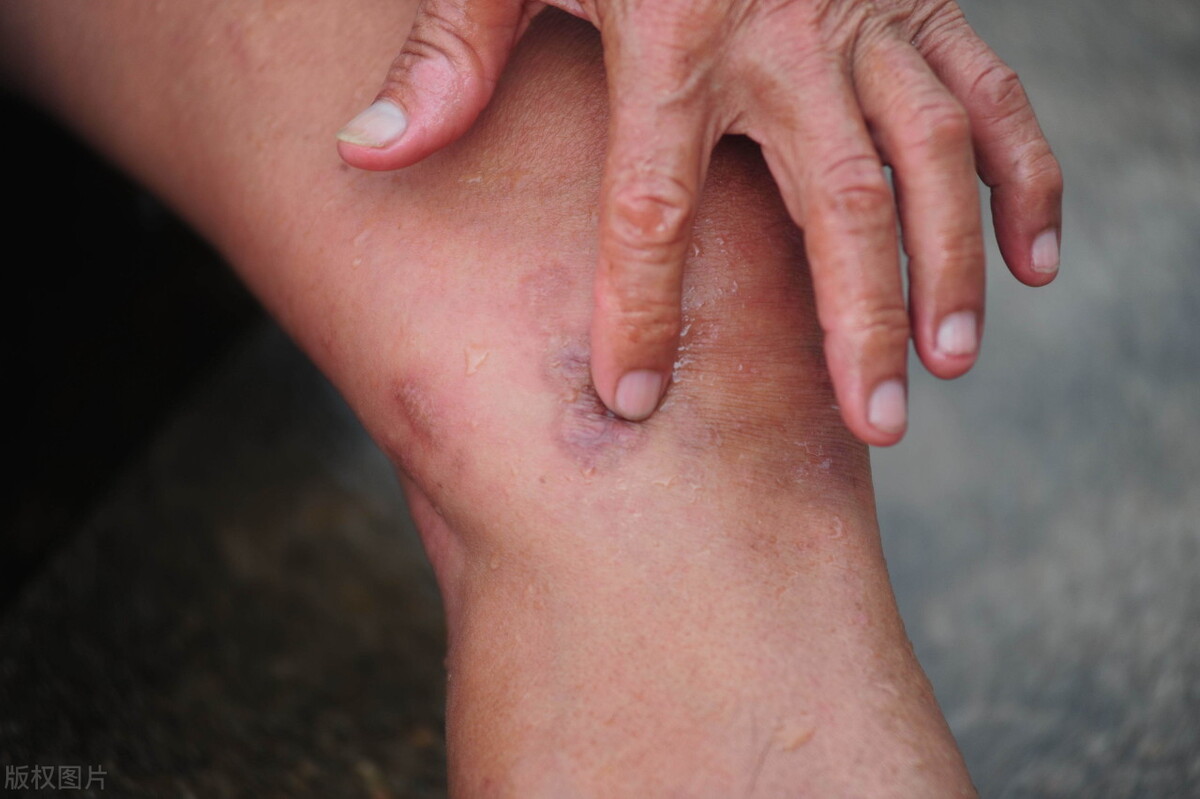

要讨论痛风能不能根治,那就需要了解下痛风是什么?从现代医学的角度看,痛风是一种代谢性疾病,是因为体内的尿酸过高,沉积到关节上形成尿酸结晶,引起关节肿胀,无菌性发炎的一种关节炎症。

而在中医上说,人体是一个整体,痛风是痹症,是关节中的湿邪热阻所致。为什么痛风喜发在下肢关节,这是因为湿性趋下,而肝的疏泄能力下降的时候,往往是痛风最频繁发作的时候。

痛风是湿邪热阻所致,而痛风往往都喜欢找上大口吃肉、大碗喝酒的男人。这是因为肉生湿,酒产热,一湿一热,那痛风怎么能不找上你呢?